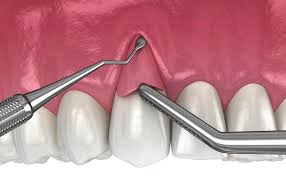

3.2 Profesyonel periodontal tedavi

- Diş taşlarının ve plakların düzenli olarak temizlenmesi (scaling ve root planing).

- İlerleyen vakalarda periodontal cerrahi, dişeti greftleri ve flep operasyonları uygulanabilir.